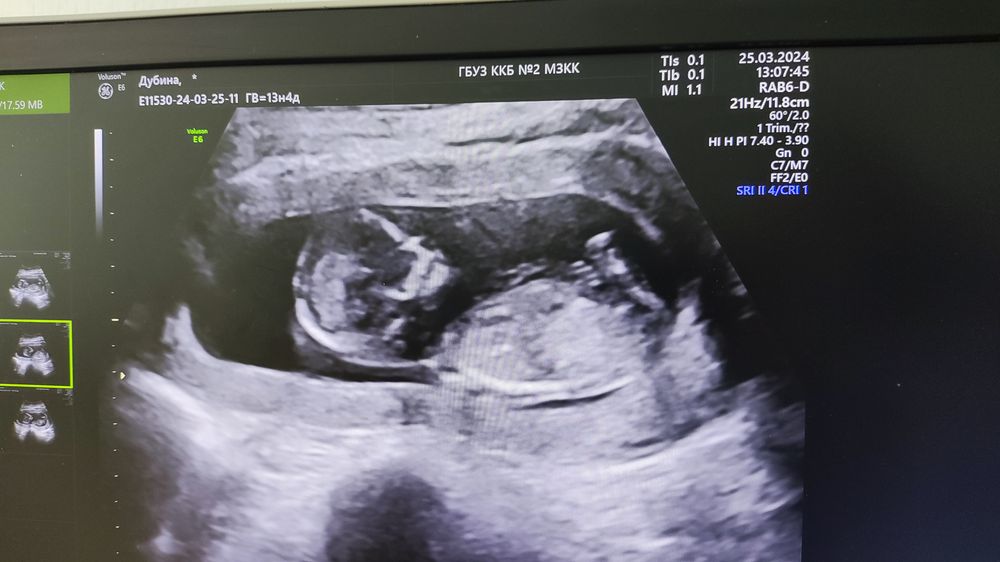

Фото с УЗИ

Вот мы и прошли 1 скринг официально и полностью) кровь сдали, УЗИ сделали. Малыш долго не хотел показывать личико, пришлось погулять по этажам)

По показателям все отлично. Разрешили сделать фото с экрана. Ну и вообщем по нему с полом все ясно😉

По УЗИ уже 13,4